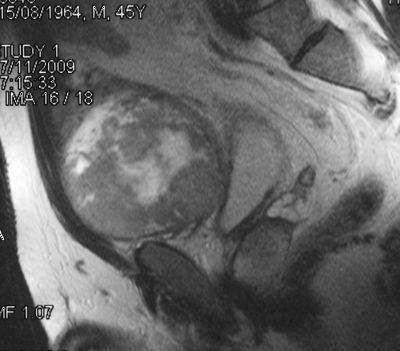

Предпузырная саркома